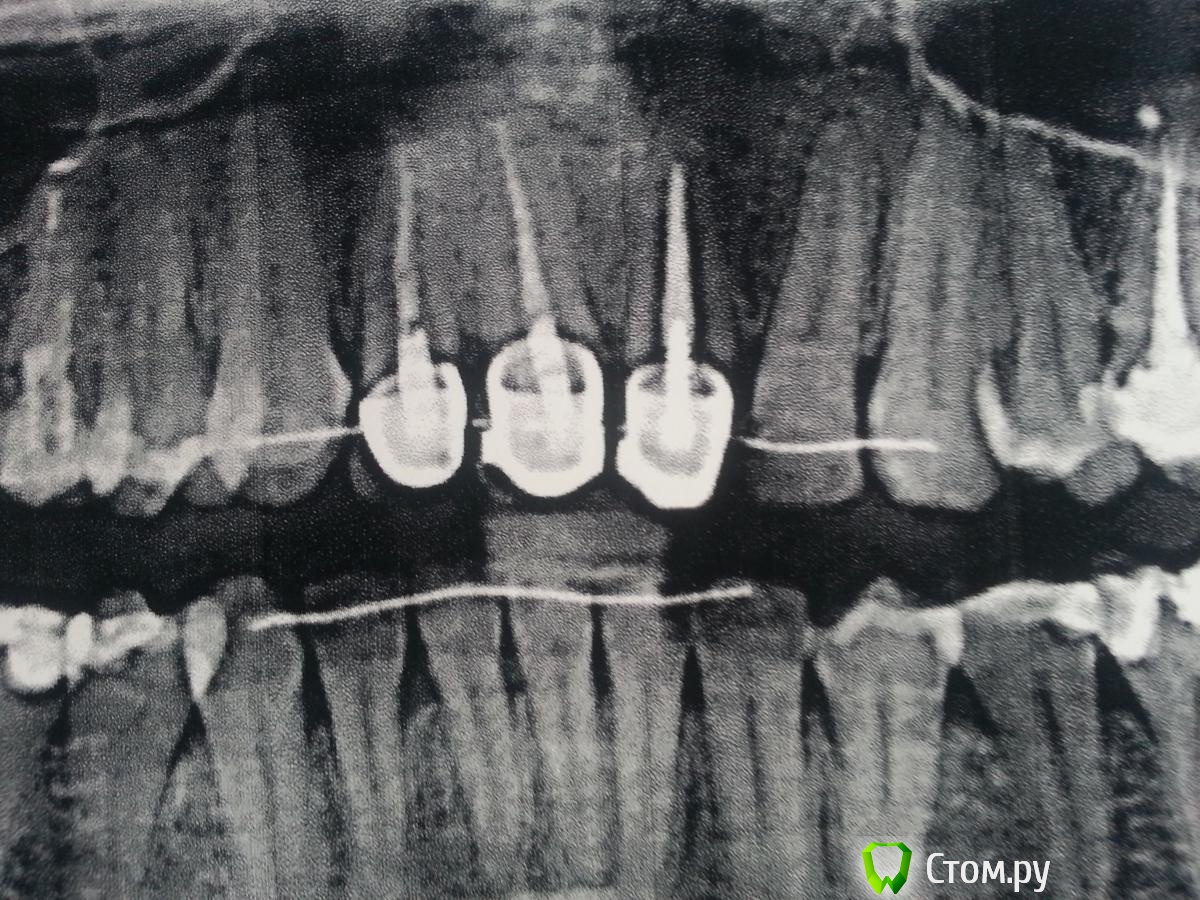

Flamma Опубликовано 6 июня, 2014 Автор Поделиться Опубликовано 6 июня, 2014 Насколько я поняла, мне поставили временные вкладки и коронки. Первые металлокерамические коронки ставили более 10 лет назад, кроме эстетики ничего не смущало, не беспокоило. Год назад сняли брекеты (носила 1г 8м), сейчас занялась заменой коронок.Врач только в вск, хотелось бы для себя хотя бы общее понимание - есть проблема или нет.Снимок прикладываю, сделан ДО снятие первых коронок. К сожалению иного нет. Ссылка на комментарий

Flamma Опубликовано 8 июня, 2014 Автор Поделиться Опубликовано 8 июня, 2014 по итогу врач сказала, что это последствия использования пломбировочных материалов. Будем перед коронками их подготавливать. Всем спасибо. Ссылка на комментарий